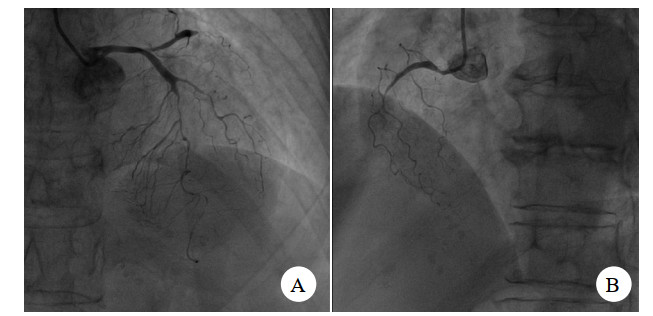

入院后考虑患者起病11 h,仍有胸痛,且心电图Ⅱ、Ⅲ、avF ST段上抬,故有急诊介入治疗手术指征,遂与患者家属交代病情,签署知情同意书后安排急诊介入手术。急诊介入过程见图 2、图 3。

| 图 2 患者急诊造影检查图像 |

患者冠脉造影提示:①前降支中远端弥漫狭窄80%~90%,第一对角支:全程弥漫狭窄70%~80%,前降支及对角支远端TIMI血流2~3级;前降支逆向有侧支循环提供;②回旋支:近端狭窄85%,回旋支中段闭塞,钝缘支近端闭塞,TIMI血流0级;③右冠状动脉:中段以远闭塞,TIMI血流0级。考虑三支冠脉严脉痉挛。术中予去甲肾上腺素维持下予冠脉内注射硝酸甘油,硝普纳后患者冠脉痉挛解除,冠脉内注入尿激酶原20 mg抗栓,经处理后患者冠脉痉挛解除。